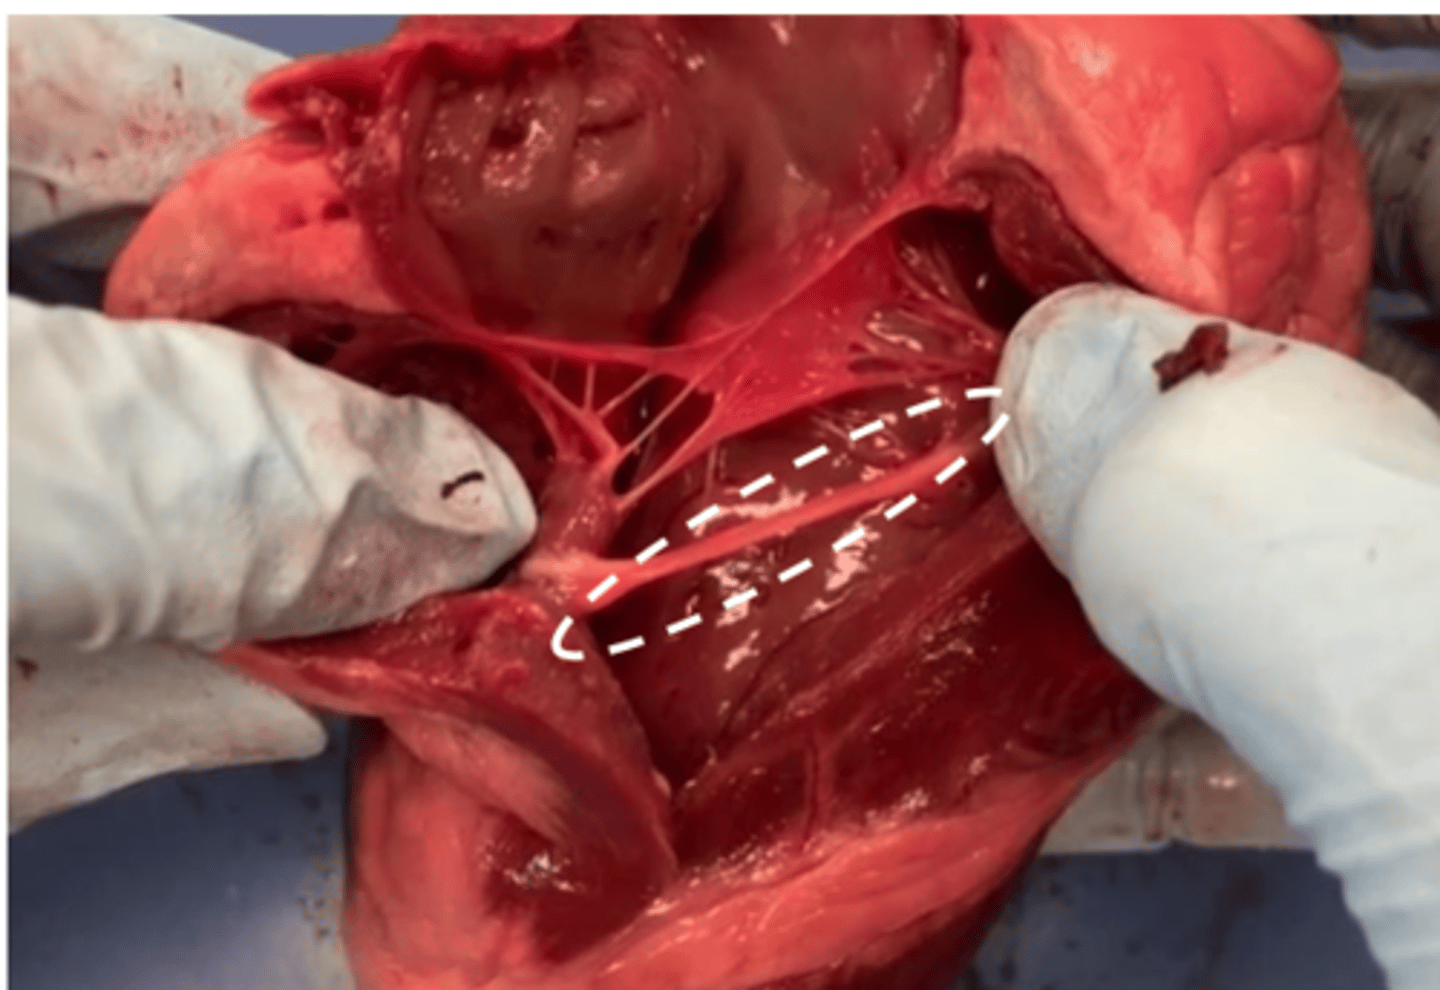

moderator band

found only on the right ventricle (you can find this only on the real heart model)

<p>found only on the right ventricle (you can find this only on the real heart model)</p>